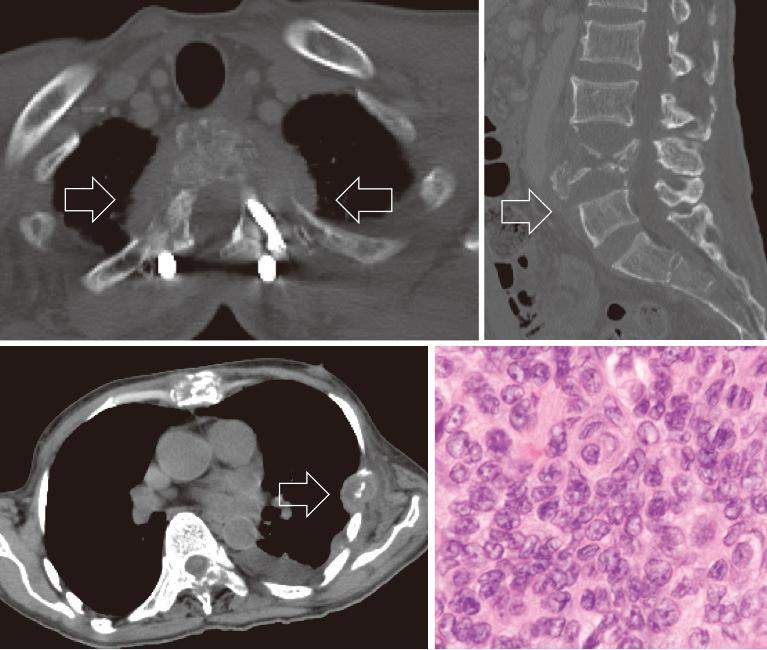

Meningioma is typically considered to be a benign tumor. Malignant transformation and metastasis of meningiomas are rare. Moreover, most meningiomas are intracranial, and there are few reports on intraspinal meningiomas. This report aimed to describe the clinical features and pathological findings of a case of malignant transformation and distant metastasis of intraspinal meningioma, with a review of the literature. A 44-year-old man with a bilateral lower limb paresis was diagnosed with an intradural extramedullary tumor of the thoracic spine. Primary tumor resection was performed, and the histological findings revealed atypical meningioma. The meningioma recurred 2 years after the primary surgery, and a second resection was performed, but only partial resection was possible because of decreased motor evoked potential. At age 48, the patient's lower limb weakness returned, and a third resection was performed, and the histological finding remained atypical meningioma. At age 54, the tumor increased and stereotactic irradiation was performed. At age 60, the patient was diagnosed with metastatic tumors of the rib, lumbar vertebra, cervical spine, and sacrum. Biopsy of the rib metastatic tumor was performed, and the histological findings revealed anaplastic meningioma. This case is the first report of an intraspinal meningioma that transformed from atypical to anaplastic meningioma with distant hematogenous metastasis.

脑膜瘤通常被认为是一种良性肿瘤。脑膜瘤的恶性转化和转移很少见。此外,大多数脑膜瘤位于颅内,关于脊髓内脑膜瘤的报道较少。本报告旨在描述一例脊髓内脑膜瘤恶性转化并远处转移的临床特征和病理结果,并对文献进行综述。一名44岁双侧下肢麻痹的男性被诊断为胸段脊柱硬脊膜外髓外肿瘤。进行了原发肿瘤切除术,组织学检查结果显示为非典型脑膜瘤。脑膜瘤在初次手术后2年复发,进行了二次切除,但由于运动诱发电位降低,只能进行部分切除。48岁时,患者下肢无力复发,进行了第三次切除,组织学检查结果仍为非典型脑膜瘤。54岁时,肿瘤增大,进行了立体定向放射治疗。60岁时,患者被诊断为肋骨、腰椎、颈椎和骶骨转移瘤。对肋骨转移瘤进行了活检,组织学检查结果显示为间变性脑膜瘤。该病例是首例脊髓内脑膜瘤从非典型转变为间变性脑膜瘤并发生远处血行转移的报道。